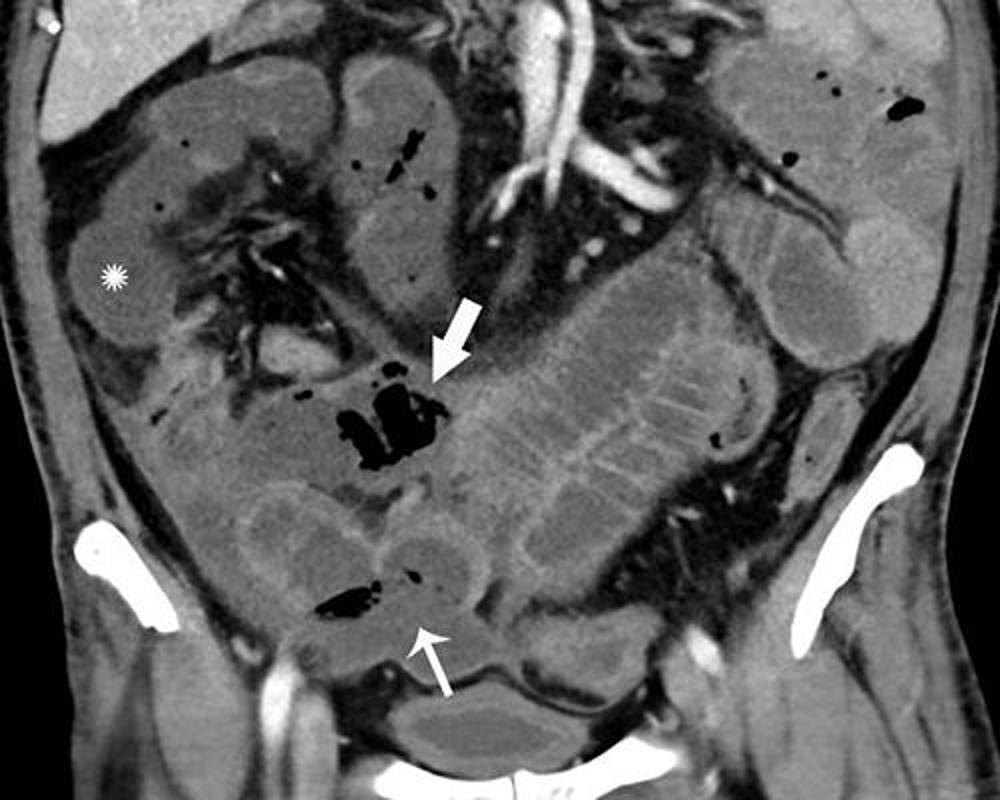

Figure 2. Coronal CT of the abdomen and pelvis with IV contrast in a 47-year-old man with abdominal tenderness demonstrates typical findings of mesenteric ischemia and infarction, including pneumatosis intestinalis (arrow) and non-enhancing bowel (*). Frank discontinuity of a thickened loop of small bowel in the pelvis (thin arrow) is in keeping with perforation.